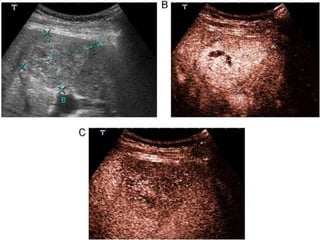

Fig.3.1 . QUISTES HEPÁTICOS. (0,8mm – 1.2mm).

Fig.3.1 . QUISTESHEPÁTICOS. (0,8mm – 1.2mm).